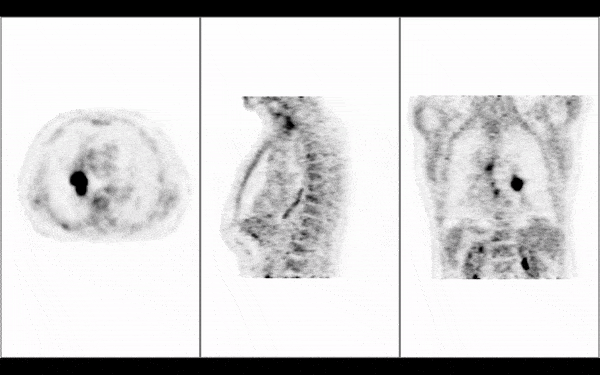

• Fuse and overlay multiple images such as PET/CT fusion